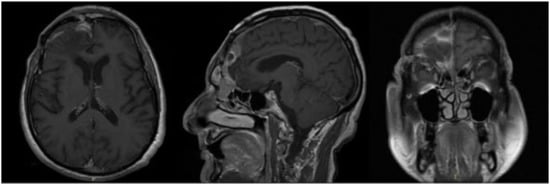

2. Case Report

| Present case | Rectus femoris and fascia lata (1) | Atypical meningioma (1) | Sphenoidal planum (1) | - |